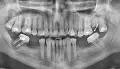

7 месяцев назад мне было проведено депульпирование 46-го зуба. Вначале несколько дней боль была достаточно сильной, потом слабее, но до конца не проходила, зуб оставался чувствительным при надавливании. Поставили временную коронку, чувствительность уменьшилась и 3 месяца назад поставили уже постоянную коронку. При этом при жевании были ноющие боли.

По рекомендации ортопеда пошла, менять пломбу на 47-м зубе. Оказалось при лечении, что кариес глубокий и нерв проходит очень близко. Было решено нерв пока не удалять, если не будет после лечения усиления болей. В течение пары недель были спонтанные довольно сильные болевые ощущения, возникающие в покое, но непонятно было 46-й или 47-й зуб болит. Теперь опять осталась чувствительность 46-го зуба при надавливании и жевании. На этой стороне практически из-за этого не жую.

Чтобы определить причинный зуб, из-за которого возникают боли, следует сделать компьютерную томографию.

Исходя из данного снимка, можно сказать, что из-за выведения пломбировочного материала за верхушки корней зуба вы чувствуете дискомфорт и болезненность при жевании. Купировать данное состояние можно нестероидными противовоспалительными лекарственными препаратами (согласно инструкции) или удалением зуба.

• Зуб слева на фото это, похоже, 47-й зуб, то есть нижний правый второй моляр. На ортопантомограмме определяется объемное воспаление, выведение пломбировочного материала в переднем корне и не до верхушки запломбирован канал дистального корня. Кроме того, из-за нарушения окклюзии зуб имеет мезиальный наклон.

• Необходим осмотр и прицельный рентгеновский снимок зуба или компьютерная томография. На данном снимке не четко видно периапикальную область за верхушками корней зуба и не ясно есть ли там воспалительный процесс или нет.